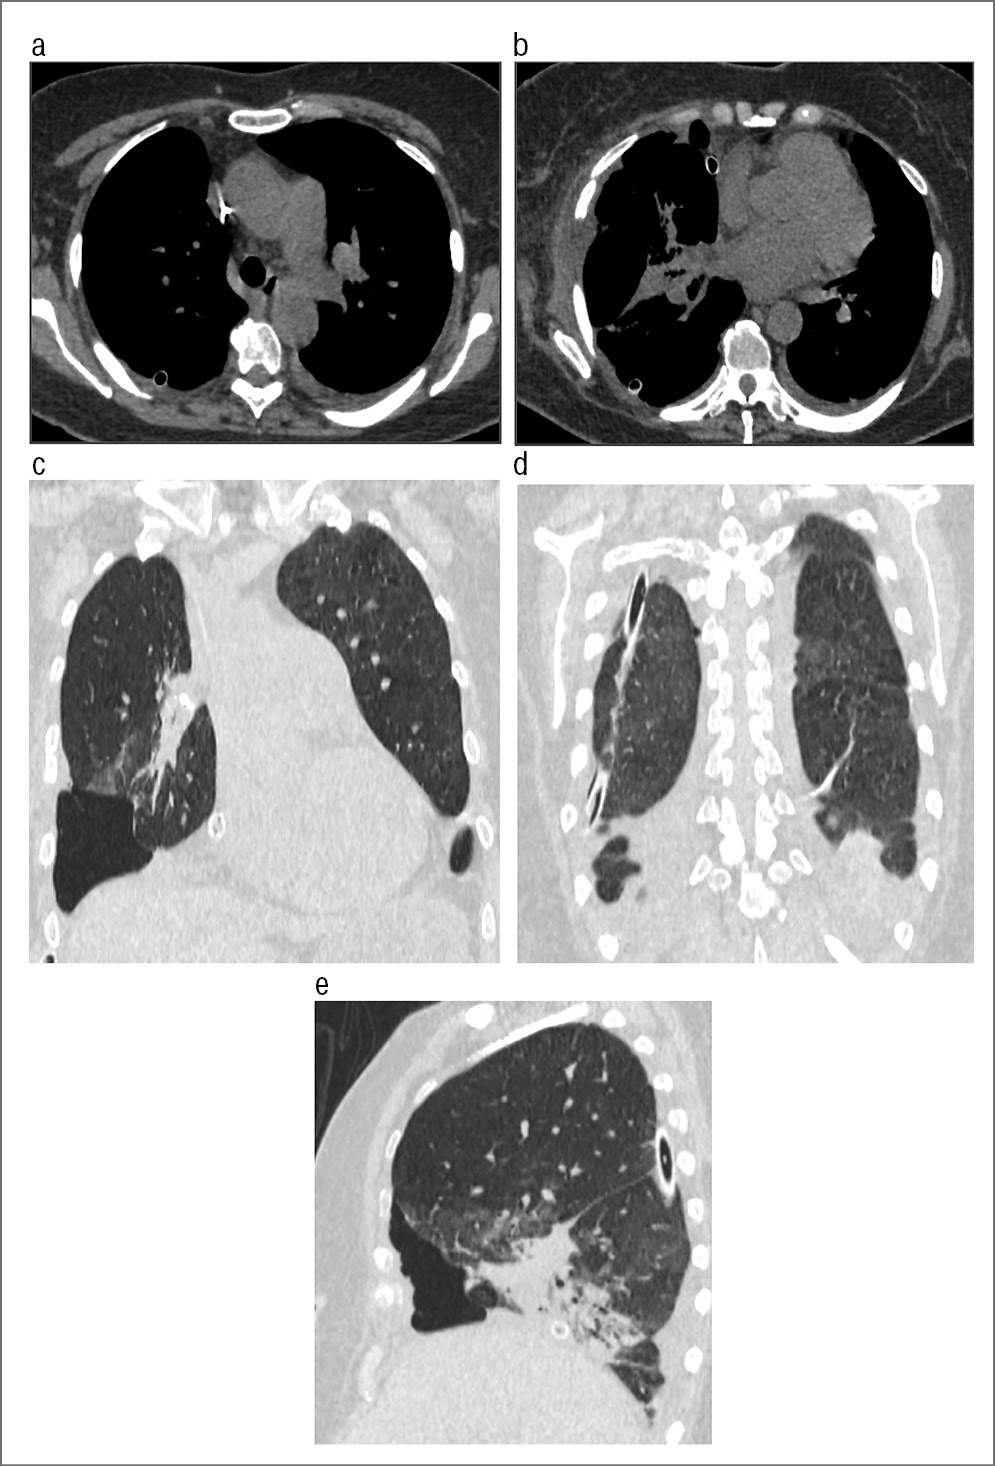

Пациент М., 77 лет. Диагноз: гигантское новообразование левого гемиторакса. Жалобы на чувство тяжести в левой половине грудной клетки, одышку при незначительной физической нагрузке, сухой кашель, потерю массы тела за последний год на 6 кг. Анамнез: со слов пациента известно, что в 1999 г. впервые при рентгенографии выявлено образование нижней доли левого легкого (данные обследования отсутствовали, характер и исходная локализация образования неизвестны). По этому поводу пациент регулярно не обследовался и у врача не наблюдался. В 2014 г. стала нарастать одышка. Поступил в отделение торакальной хирургии УКБ №1 для дообследования и оперативного лечения. При проведении МСКТ с контрастированием выявлено гигантское образование левого гемиторакса с гетерогенной структурой, неравномерно накапливающее контрастное вещество. Опухоль смещала вправо средостение, которое компримировало легочные сосуды без признаков инвазии. Перикард также интактен (рис. 9, a–c).

Рис. 9. МСКТ: а – аксиальная проекция; b, c – МПР во фронтальной и сагиттальной проекциях. Визуализируется гигантское образование левого гемиторакса неоднородной структуры, неравномерно накапливающее контрастное вещество.

Опираясь на данные обследования, преимущественно на результаты МСКТ, при котором не выявлено признаков опухолевой инвазии структур средостения, решено провести торакотомию слева. Однако установить исходную локализацию опухоли в силу ее огромных размеров не представилось возможным. Проведена операция по удалению гигантской опухоли диафрагмы (рис. 10, a–c) с краевой резекцией верхней доли левого легкого. При гистологическом исследовании: нейрофиброма.